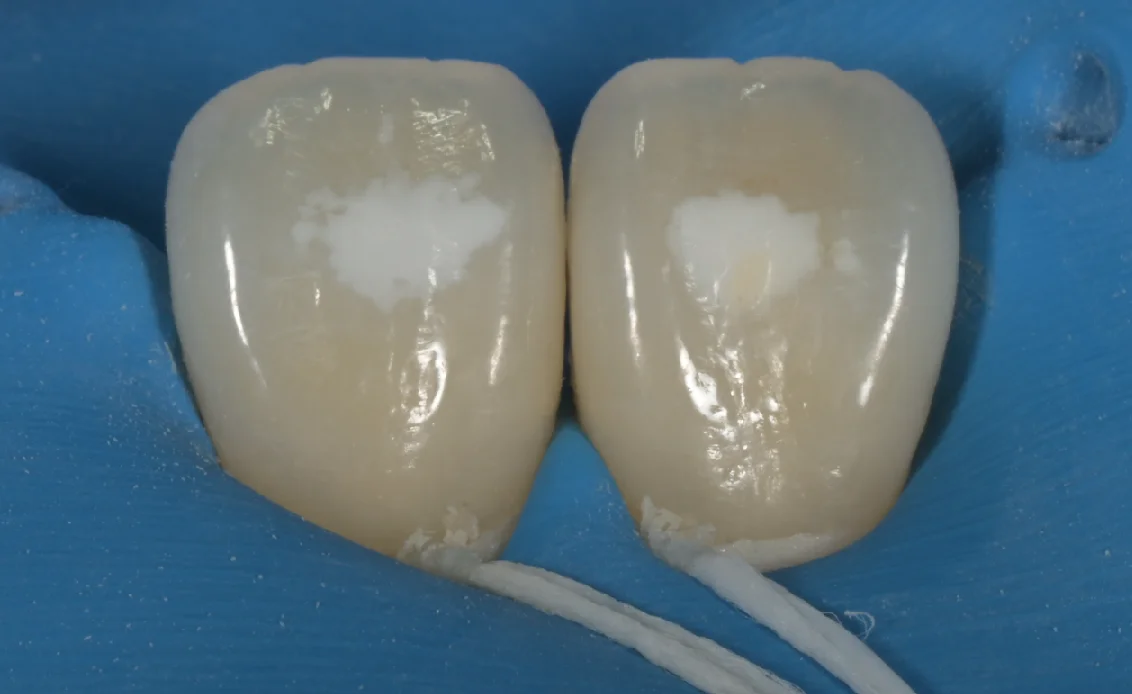

そもそもホワイトスポットとは何かというと、

こんな感じで、歯の表面に白い点があることってありませんか?

この部分をホワイトスポットと言います。

ご存知の方も多いと思いますが、非常に強力な薬液ですので、このように…

ゴムのマスク(ラバーダム)を装着していきます。

こうやって歯茎に間違ってもつかないように保護する感じですね。

そこにこのように塩酸をつけて、塗りこんで処理していきます。